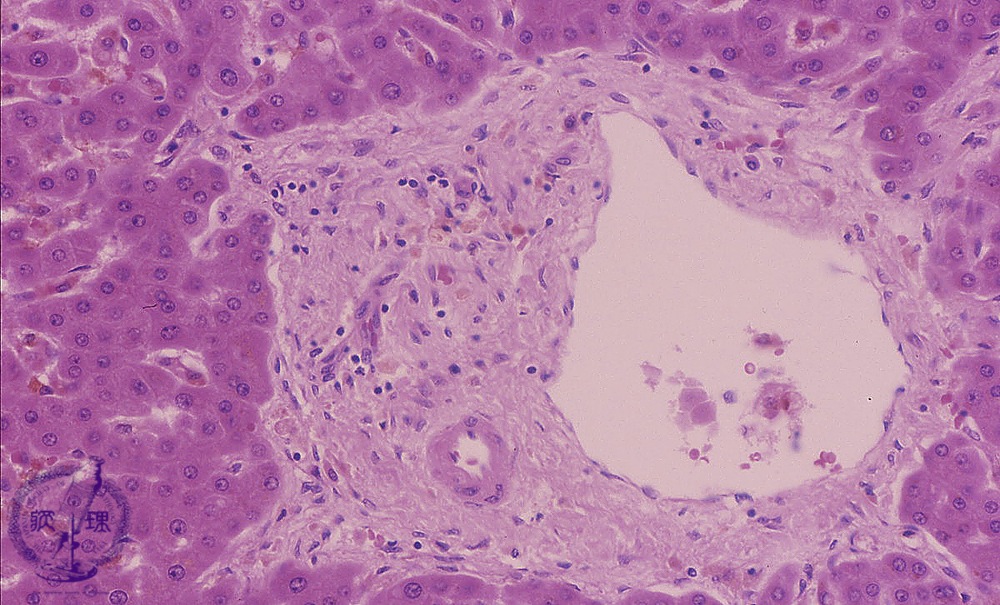

• 10.Liver

• (11)Transplantation rejection

Microscopic image (HE stain, high power view): Slightly expanded, mid-sized portal areas contain branches of portal vein and hepatic artery, but interlobular bile ductules are absent. Inflammatory cell infiltration is minimal.